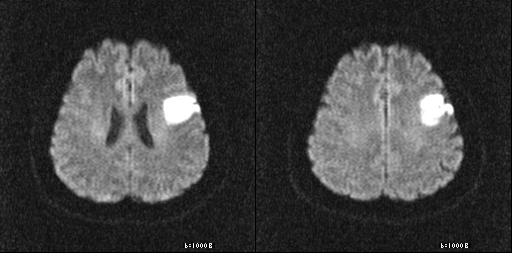

뇌경색은 뇌의 혈관이 막혀서 뇌에 산소와 영양분이 공급되지 않게 되는 상태를 의미합니다. 이런 혈액 공급이 차단되면 뇌세포가 손상되거나 사멸하게 됩니다. 급성 뇌경색은 시간이 지남에 따라 위험성이 증가하므로, 초기 증상을 빠르게 인식하는 것이 필요합니다. 뇌경색은 주로 고혈압, 고지혈증, 당뇨병 등의 만성 질환과 연관이 있습니다.